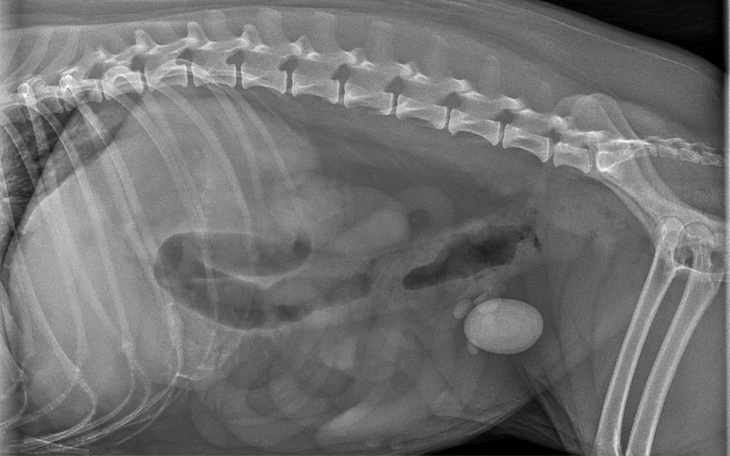

Niestety po badaniu rtg okazało się, że w Jej pęcherzu znajduje się kamień wielkości 4,6x2,5 cm... Przeogromne jajo pilnie do operacji inaczej Pchełce może w każdym momencie pęknąć pęcherz, co oznacza śmierć w straszliwych męczarniach.